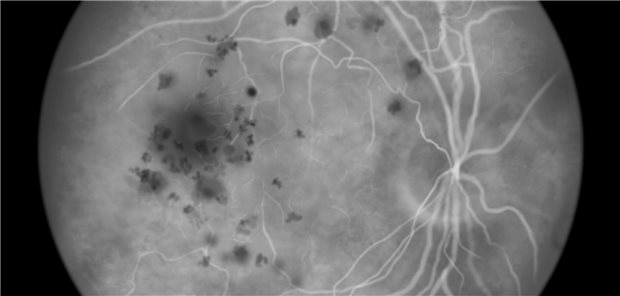

Die nach einem Jahr erzielten Verbesserungen beim Visus und den Netzhautbefunden konnten aufrechterhalten werden. Der Zugewinn an bestkorrigierter Sehschärfe war mit beiden Medikamenten ähnlich: Durchschnittlich 3,7 und fünf Buchstaben mehr als zu Studienbeginn konnten mit Faricimab Behandelte nach zwei Jahren erkennen, während es unter Aflibercept 3,3 und 5,2 waren.

Neovaskuläre altersbedingte Maculadegeneration

Faricimab: Nach zwei Jahren weiterhin Verbesserungen beim Visus